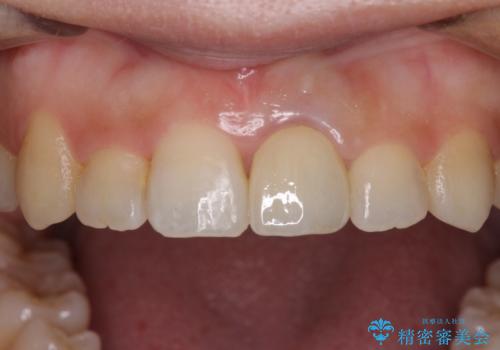

前歯のクロスバイトと変色した歯 ワイヤー矯正とセラミック治療

- 前歯のクロスバイトと神経を取り除いた後に変色してしまった前歯を気にして来院された患者様です。

ワイヤー矯正により矯正治療を行った後に、前歯の補綴治療を行うこととしました。

変色してしまった前歯は、反対側の歯と比べて歯肉が覆い被さっていたため、骨整形を含めた歯周外科処置を行い、歯肉ラインを整えることとしました。